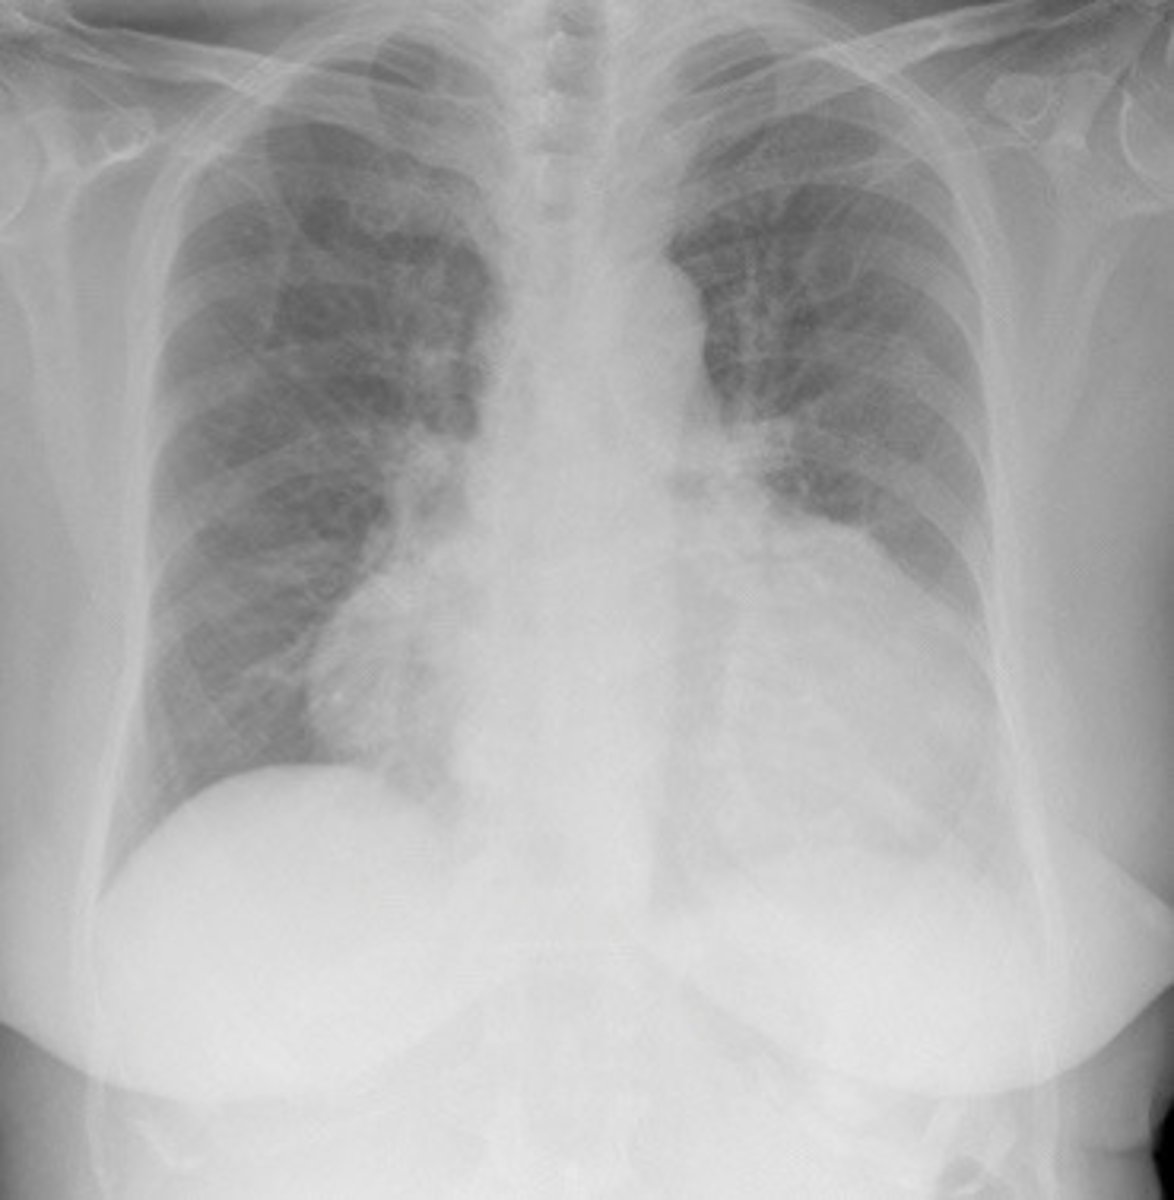

What findings on a CXR may indicate IHD

Cardiomegaly on CXR

What does this image show